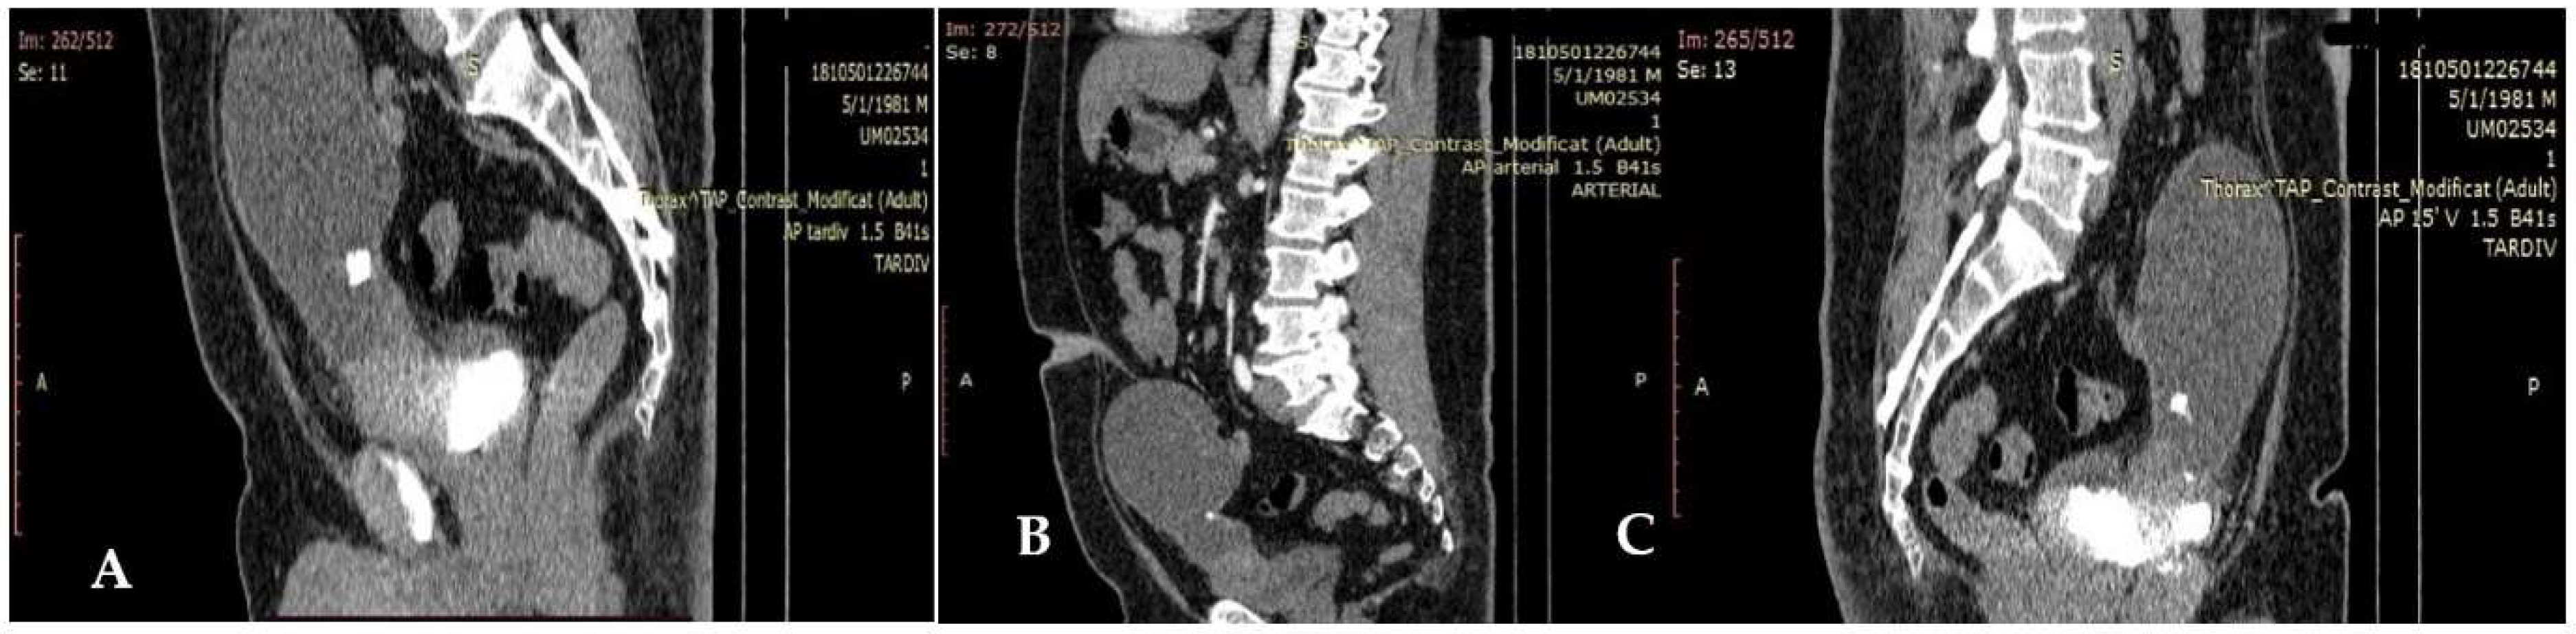

2.2. Imaging Findings